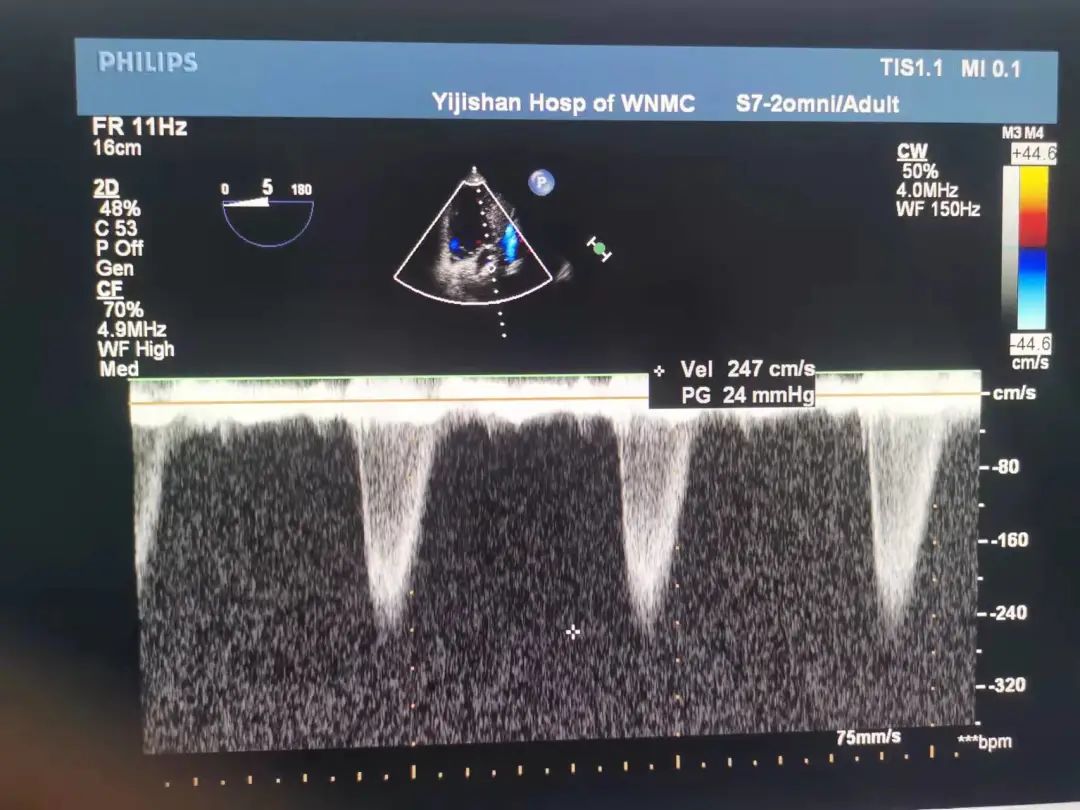

术后食道超声

经猪尾导管复查造影:瓣膜支架系统膨胀良好,未见瓣周漏,冠脉显影正常,食道超声提示瓣膜工作正常,压差解除,无瓣周漏。